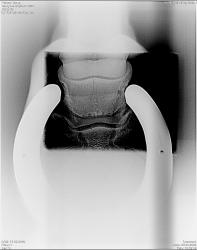

Желательно представление изображений, полученных при использовании данной системы.

Спасибо за представленные изображения.

По поводу изображения шейного отдела позвоночника, произведенного в боковой проекции. Хорошо видны позвонки, межпозвонковые щели, отлично дифференцируются воздухоносные ячейки сосцевидного отростка височной кости, но вот сама пирамида височной кости - увы не дифференцируется - "пропала", возможно из большой плотности. Посему я и задаю вопрос об экспонировании в условиях органоавтоматики?

Кроме того явно страдает изображение С6.

В программном обеспечении имееются фильтры с помощью которых можно улучшить изображение в зависимости от проводимых исследований.

В любом случае в программном обеспечении изображения гораздо лучше, чем преобразованные в jpg.

Спасибо за разъяснения по поводу фильтров.Но коллегам врачам-лучевым диагностам, по всей видимости желательно было-бы ознакомиться с изображениями для "принятия решения":

1. Изображение черепа - прямо и боком.

2. Изображение почек и мочевыводящих путей в условиях внутривенной урографии.

3. Изображение костей - тазобедренный сустав, коленный сустав, стопа.

Еще раз спасибо за представленные изображения, но на изображении кисти и лучезапястного сустава в прямой проекции создается впечатление, что "снимок недобит" - мягкий, и по качеству "проигрывает рентгенограмме".